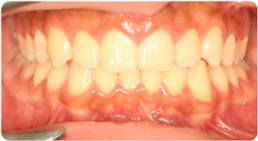

Each case shows the front view and an arch or side view, before and after BioLign Method-guided treatment.

All cases treated within 6–12 months.

Protruding front teeth aligned and brought into ideal occlusion